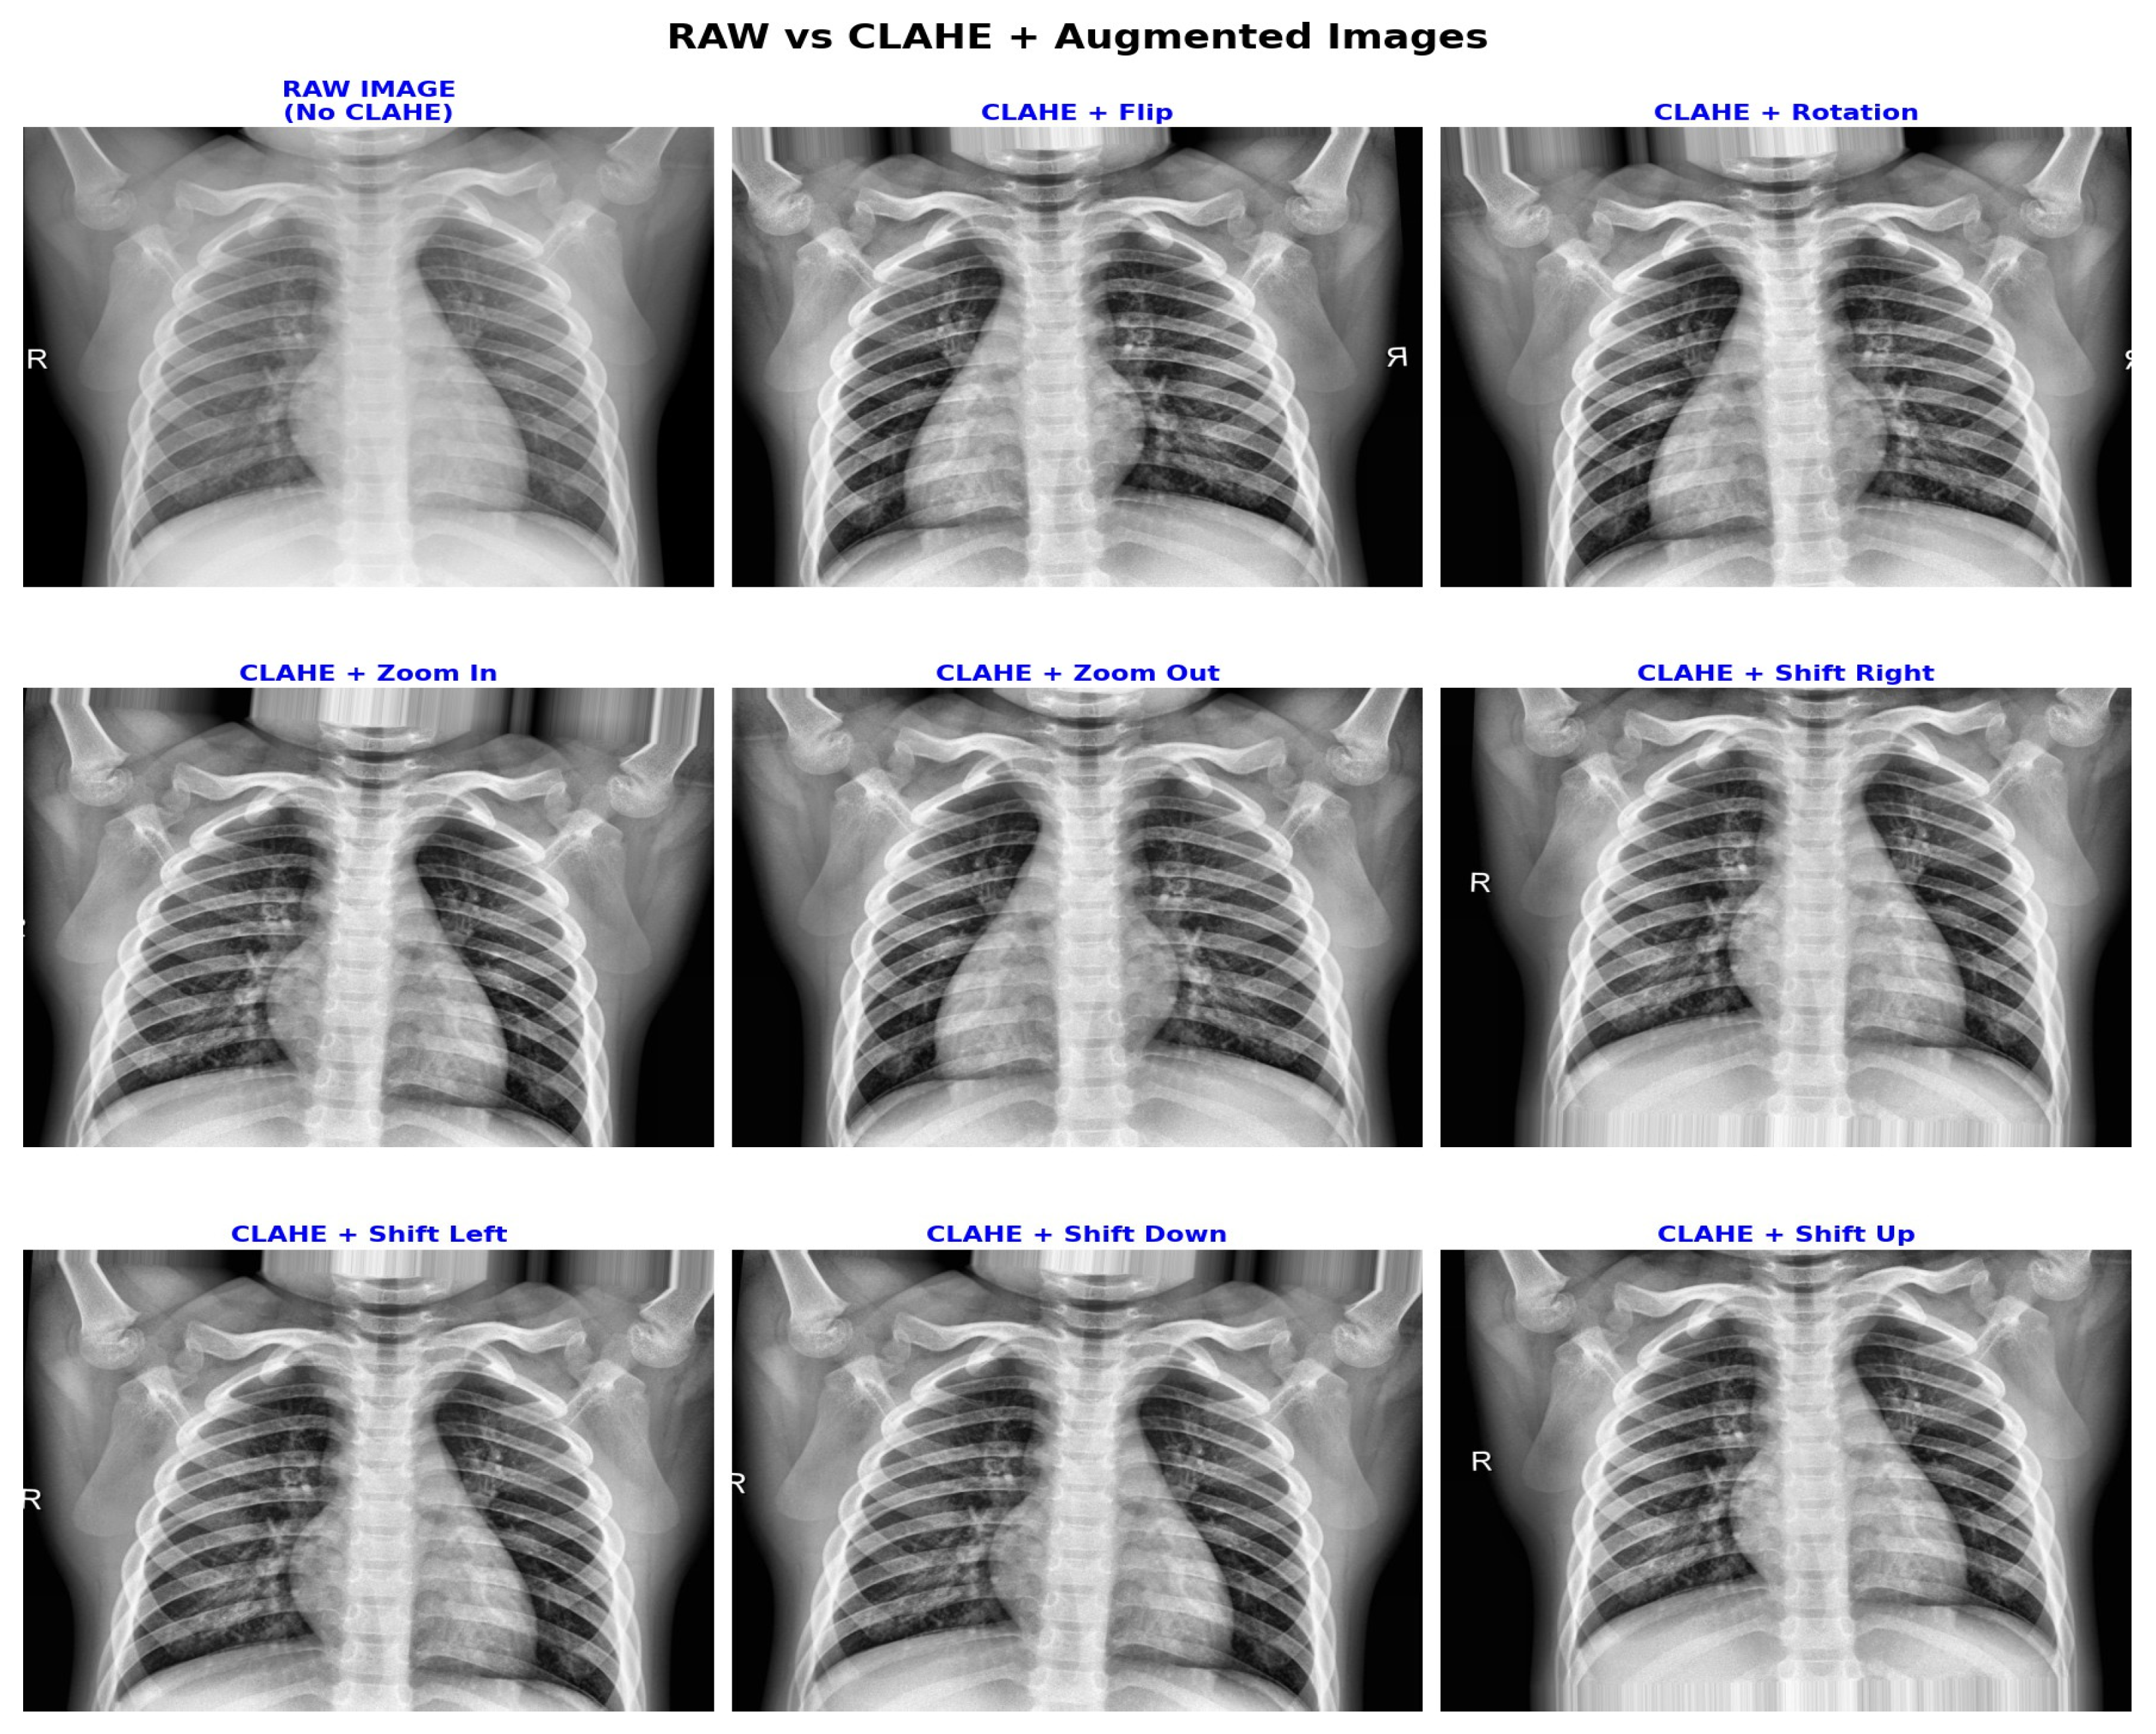

3.2. Clinically Aware Data Augmentation

3.3. Contrast Enhancement with CLAHE

| Augmentation | Range/Setting | Clinical Purpose |

|---|---|---|

| CLAHE | clipLimit = 2.0, grid = 8 × 8 | Enhances local contrast in low-density lung regions, improving feature visibility. |

| Horizontal Flip | 50% chance | Simulates left/right orientation variable, compromising diagnostic integrity. |

| Translation | Max ±12 pixels (approximately 5%) | Models minor patient positioning variable image acquisition. |

| Rotation | Max ±5° | Preserves heart silhouette stability with slight orientation tolerance. |

| Zoom | 95–105% | Simulates small magnification changes, introducing anatomical distortion. |